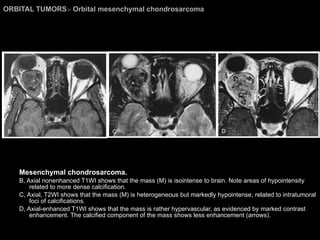

Orbital mesenchymal chondrosarcoma Extremely rare More frequently in young women. Proptosis, with orbital pain, diplopia, and headache. Imaging Findings: Well-defined soft-tissue mass. Mottled, coarse calcification. Moderate, delayed contrast enhancement.  Hypo/iso T1WI and iso on T2WI (to brain).

ORBITAL TUMORS >  Orbital mesenchymal chondrosarcoma Mesenchymal chondrosarcoma.  B, Axial nonenhanced T1WI shows that the mass (M) is isointense to brain. Note areas of hypointensity related to more dense calcification.  C, Axial, T2WI shows that the mass (M) is heterogeneous but markedly hypointense, related to intratumoral foci of calcifications.  D, Axial-enhanced T1WI shows that the mass is rather hypervascular, as evidenced by marked contrast enhancement. The calcified component of the mass shows less enhancement (arrows).